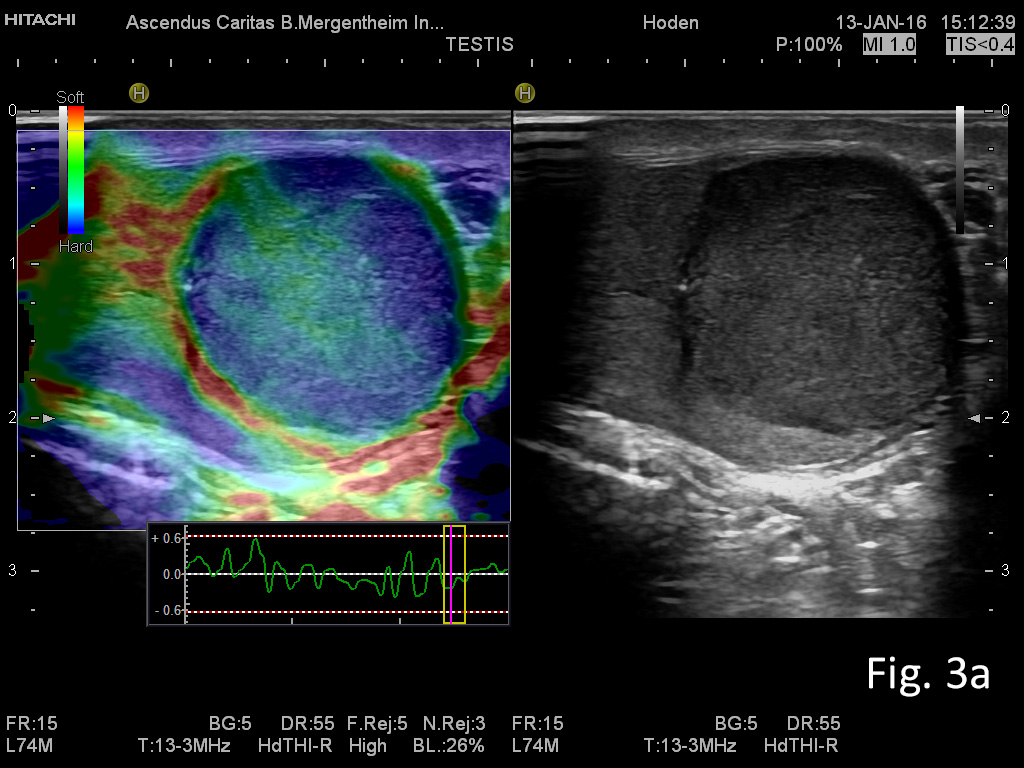

Figure 3: Imaging of the left testicle using elastography with sharp delineation of the embryonal cell carcinoma with clear stiffer elastographic delineation from the surrounding tissue (a) and CEUS with atypical neoplastic vessels and little perfusion (b).